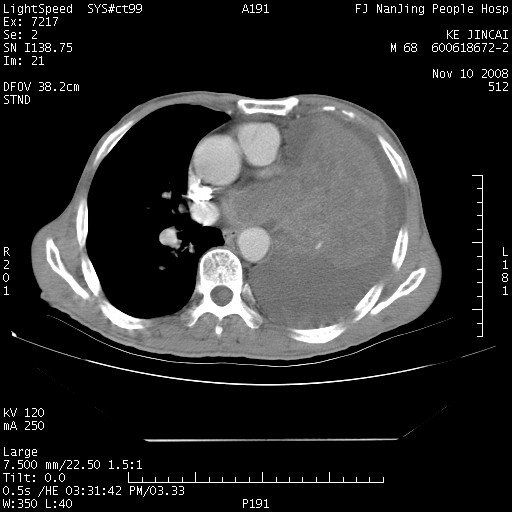

是个很有看头的病例,咋人气那么不旺?没多少人兴趣呢?这个病例几大怪:1   恶性肿瘤侵犯心肌左房怪,心肌一般不会被恶性肿瘤侵犯吧?2   左下肺均匀实变怪,内无含气,有别一般不张实变,含气肺泡完全为液体取代,而非一般不张实变的肺萎陷,冷不丁还以为是肿大的脾脏3   肿瘤本身怪,像tb肺不张4   这么有看头的病例没人气怪。呵呵。

左肺恶性肿瘤侵犯肺动脉,左心房内瘤栓,胸膜转移。

恶性肿瘤,以肺肉瘤可能大。定性诊断穿刺活检还是比较方便的。